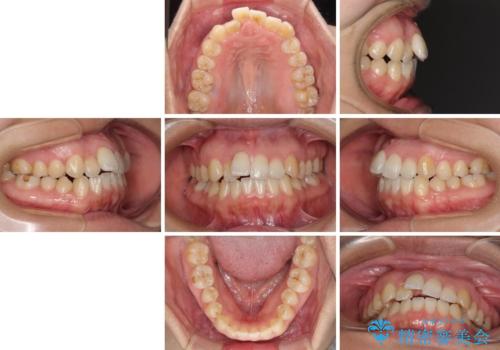

- 上下のデコボコを改善したいとのことで来院された患者様です。

近々妊娠する予定であり、極力短期間で治療したいとのことで、ワイヤー装置による非抜歯矯正治療を行うこととしました。